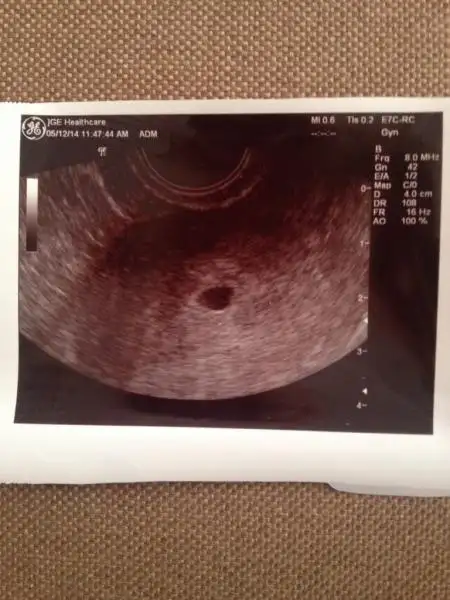

Orda bir kesemi var nee :))) kızlar doktordan geliyorum,çok şükür minik keseceğim gözüktü..5 hafta 5 günlük falan dedi.. 10 gün sonra kalp atışı inşallah Eki Görüntüle 1110634

Oyy keseye bak maşallah canim cok sevindim artık kan vermek yok :))